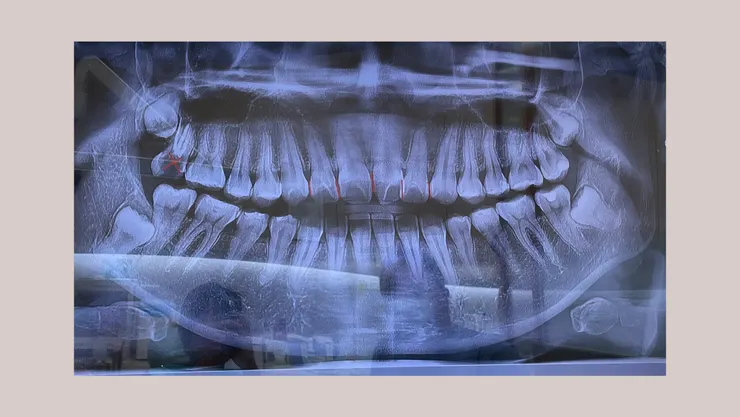

X光照🩻

X 光側面照,雖然咬合沒有太大問題,但要自然閉合嘴巴需要出一些力氣

醫生講解說明,會先透過牙套拉開牙齒距離,最後在畫紅線的幾顆牙齒進行細微的修磨,照片左上方畫叉叉的是之前根管治療的牙齒,因為已經沒有用處,後面在矯正期間會安排拔除